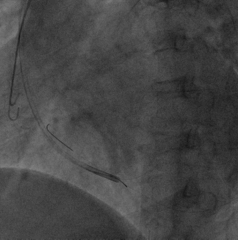

选择后侧静脉,Runthough导丝顺利通过并与心中静脉交通回到右心房,但左室4298电极无法通过狭窄处。

因4298外径在5.3F,故选用Maverick2.0X15mm预扩球囊在狭窄处给予充分扩张

扩张后电极仍无法通过

尝试心中静脉,但血管扭曲,导丝进入困难

尝试侧静脉,但远端过于狭窄,电极无法完全进入分支,测试结果不理想,只能放弃该血管

再次尝试后侧静脉,改用Sprinter Legend2.5X15mm预扩球囊扩张,可见明显腊肠样狭窄,给予28atm时方可见完全扩张

电极仍然无法通过,造影发现狭窄依然存在

尝试鞘中鞘试图通过狭窄处,但电极仍然无法通过

尝试Quantum Maverick3.0X12mm后扩球囊进行扩张

电极依然无法通过狭窄处,放弃手术?